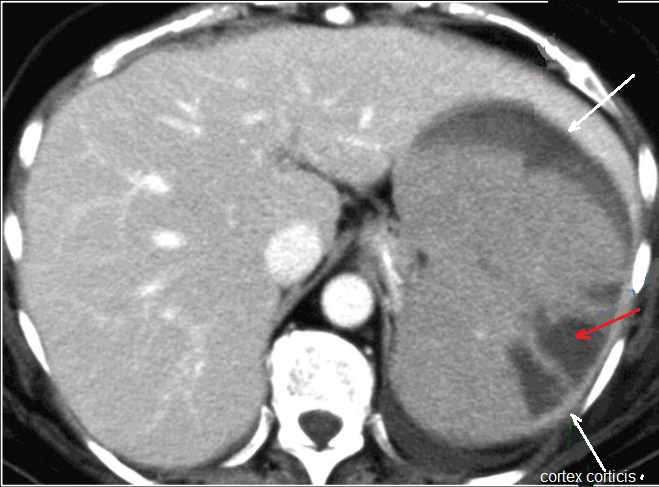

Aspect radiologique en forme de coin (

wegde sharpe ) tres hypodensite ( fleche rouge )de

contours nets, base peripherique vers le versant

capsulaire , signe de cortex corticis ( persistance

une vascularisation peripherique ) ( fleche blanche

a inferieuse ) |